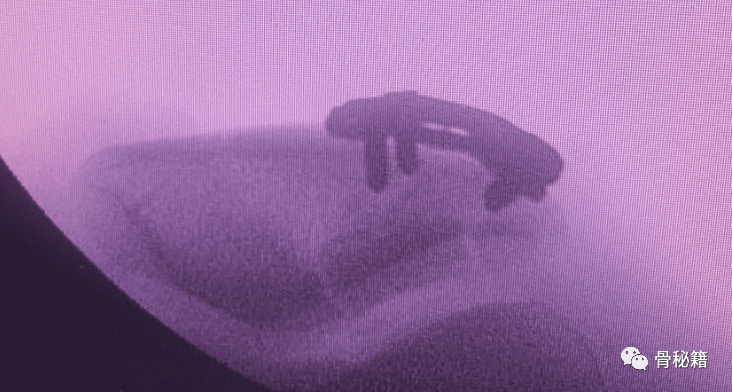

术中需要注意,应用轴位来观察关节面的复位情况,

而不是侧位来达到较好的复位效果